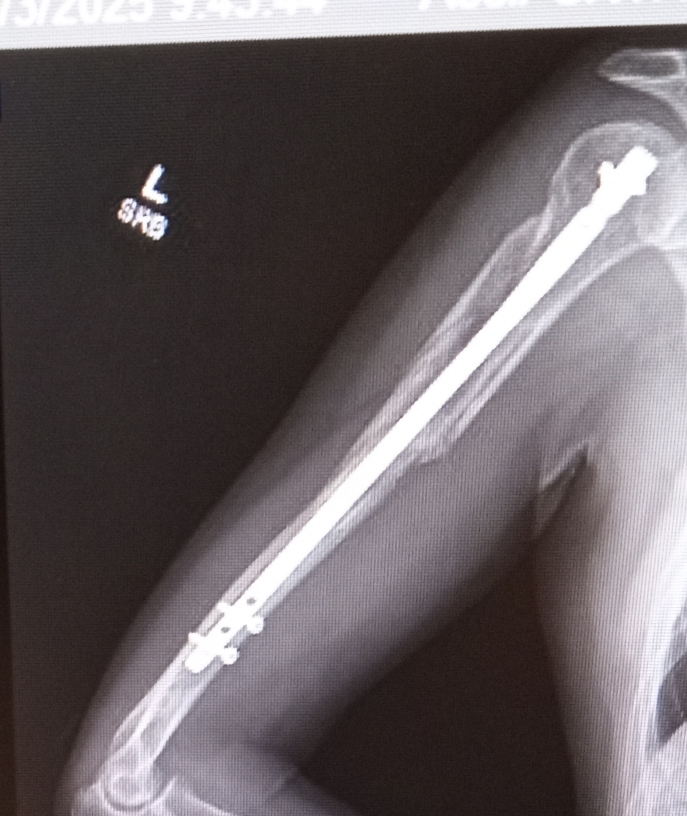

File: arm.jpg (297.5 KB)

297.5 KB

297.5 KB JPG

>>23724412

yeah I'm mostly healed up but it was rough

>>23724395

>>23724427

motorcycle accident?

>>23724952

close, car blasting out of a stop sign vs me using the crosswalk on my bicycle

I'm mostly better, some lingering nerve damage on my thumb and some aches and pains, but enough to make me realize it could be a whole lot worse

Did you get the retractable claws bonus?

>>23726037

If it was the lower arm and not upper he could've potentially done the T2 scene.

I can't even stick magnets on my limbs ;_;

ngl I really do get a kick out of the basic idea that i have metal parts, like that doofy grin the Yakuza guy has when he's low-key bragging to his flunkies about being a Shocker goon, I get that at least twice a day when I think about stuff like "my arm's specs are rated for up to 600lbs" and then I remember that aside in GITS about Batou and why your cyberarm is cool but you need a cybershoulder attached too

the other day I impressed my niece with the idea that I have mechanical parts